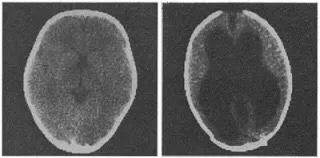

1980年12月,《科学》也讲述了一个类似的例子。有个数学系的学生脑袋比其他人的大,经过研究发现他大脑里也有积水,这些积水把脑组织挤得不到一毫米厚,而正常人的大脑皮层有4.5厘米厚。后来,这位学生顺利取得了数学学位。唉,看来数学学不好不该让脑子背锅。

右边就是该数学系高材生的大脑